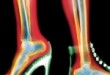

Burkulma gerilmiş veya yırtılmış bir bağ ya da kastır. Vücutta bilinen en yaygın olarak burkulan eklem, ayak bileği eklemidir. Bileğin burkulması, çoğunlukla ayağın dış kısmı üzerine kaldırabileceğinden daha fazla bir yük...